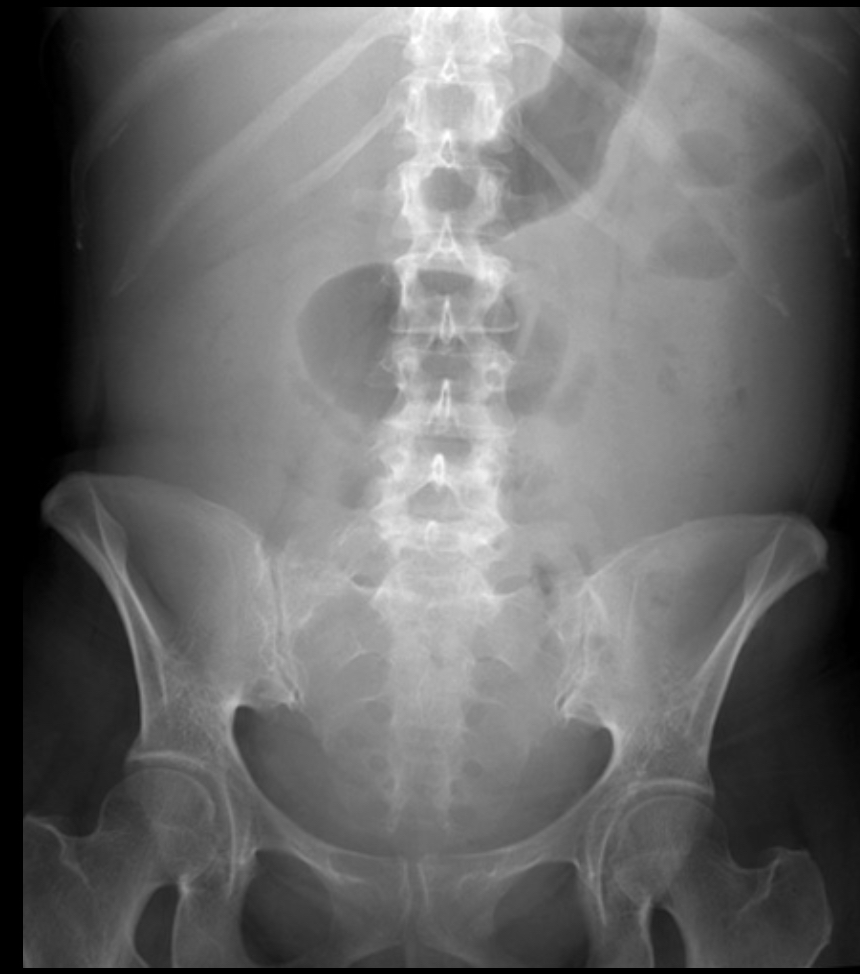

ascites

accumulation of fluid in the peritoneal cavity

radiographic appearance of ascites

wash out, overall gray

technical factors of ascites

additive (may have to increase technique)

What pathology is this?